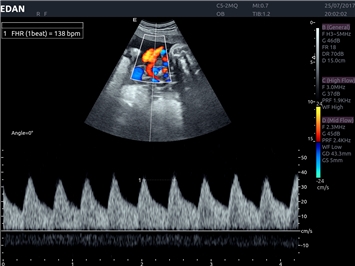

• Кардиологических исследований

Тканевой допплер:

Да

Постоянно-волновой допплер:

Импульсно-волновой допплер: